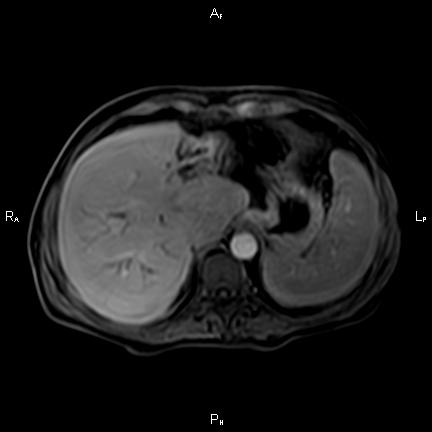

ΚΛΙΝΙΚΑ ΣΤΟΙΧΕΙΑ – ΙΣΤΟΡΙΚΟ

Ανώδυνος ίκτερος και παθολογικά ηπατικά ένζυμα. Ιστορικό πιθανής σκληρυντικής χολαγγειίτιδας

ΑΠΕΙΚΟΝΙΣΤΙΚΟΣ ΕΛΕΓΧΟΣ

Μαγνητική τομογραφία.

Οι αρχικές εξετάσεις εκλογής, όσον αφορά τον απεικονιστικό κυρίως έλεγχο, σε ασθενή προσερχόμενο στο Νοσοκομείο με αποφρακτικό ίκτερο, είναι το υπερηχογράφημα και η αξονική τομογραφία. Οι εξετάσεις αυτές έχουν αποδειχθεί ικανές να προσδώσουν έμμεσα και άμεσα στοιχεία για τη διάγνωση του χολαγγειοκαρκινώματος, όμως κυρίαρχη εξέταση για την διάγνωση του χολαγγειοκαρκινώματος είναι η μαγνητική τομογραφία (MRI, MRCP, MRA).